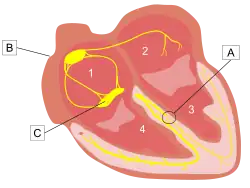

| This image shows bundle branch block where the beating rhythm is hindered, but not stopped. A blockage in Site A in the left ventricle blocks electrical signals from the atrium, causing the heart to rely on the right ventricle to maintain the correct rhythm. A:obstruction B:sinus node C:atrioventricular (AV) node 1:right atrium 2:left atrium 3:left ventricle 4:right ventricle | |

Heart block (HB)[1] is a disorder in the heart's rhythm due to a fault in the natural pacemaker.[2] This is caused by an obstruction – a block – in the electrical conduction system of the heart. Sometimes a disorder can be inherited. Despite the severe-sounding name, heart block may cause no symptoms at all or mere occasional missed heartbeats and ensuing light-headedness, syncope (fainting), and palpitations. However, depending upon exactly where in the heart conduction is impaired and how significantly, the disorder may require the implantation of an artificial pacemaker, a medical device that provides correct electrical impulses to trigger heartbeats, compensating for the natural pacemaker's unreliability, so making heart block usually treatable in more serious cases.

The human heart uses electrical signals to maintain and initiate the regular heartbeat in a living person. Conduction is initiated by the sinoatrial node ("sinus node" or "SA node"), and then travels to the atrioventricular node ("AV node") which also contains a secondary "pacemaker" that acts as a backup for the SA nodes, then to the bundle of His and then via the bundle branches to the point of the apex of the fascicular branches. Blockages are therefore classified based on where the blockage occurs – namely the SA node ("Sinoatrial block"), AV node ("AV block" or AVB), and at or below the bundle of His ("Intra-Hisian" or "Infra-Hisian block" respectively). Infra-Hisian blocks may occur at the left or right bundle branches ("bundle branch block") or the fascicles of the left bundle branch ("fascicular block" or "Hemiblock"). SA and AV node blocks are each divided into three degrees, with second-degree blocks being divided into two types (written either "type I" or "II" or "type 1" or "2"). The term "Wenckebach block" is also used for second-degree type 1 blocks of either the SA or AV node; in addition, second-degree blocks type 1 and 2 are also sometimes known as " Mobitz 1" and "Mobitz 2".